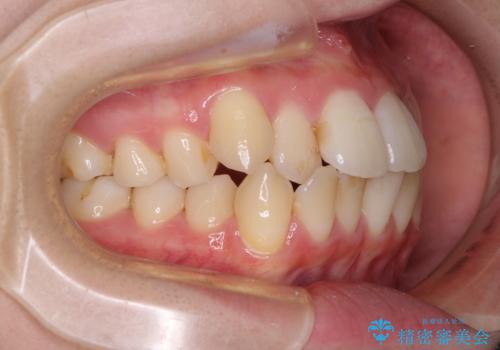

【モニター】前歯の前突感とクロスバイトをインビザラインで改善

- 前歯の突出感とクロスバイトが気になり、インビザラインによる矯正治療を希望して来院された患者様です。

上顎側切歯(上の真ん中から2番目の歯)が舌側転位している場合、インビザラインでは仕上げきれないことが多く、更には無理して動かそうとすると歯髄壊死を起こすリスクが高いと言われています。

インビザラインで歯列を移動する前に、上顎前歯をワイヤー矯正で整え、その後上下歯列をインビザラインにて矯正治療を行うこととしました。

舌側転位している側切歯特有の、切縁の位置が不揃いであったり、根元が内側に引っ込んだ状態であったりという、インビザライン独特の仕上がりになることなく、きれいに整った歯列とすることができました。